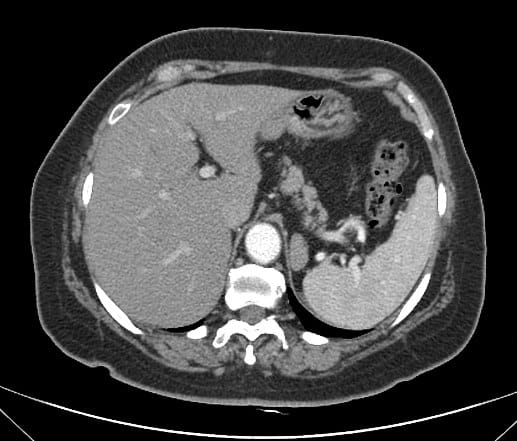

Túi thừa dạ dày

» Thông tin: Nữ giới – 50 tuổi.

» Lâm sàng: Kiểm tra sức khỏe.